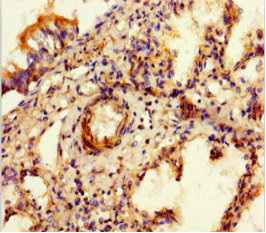

Immunohistochemistry of paraffin-embedded human lung tissue using CSB-PA814217LA01HU at dilution of 1:100